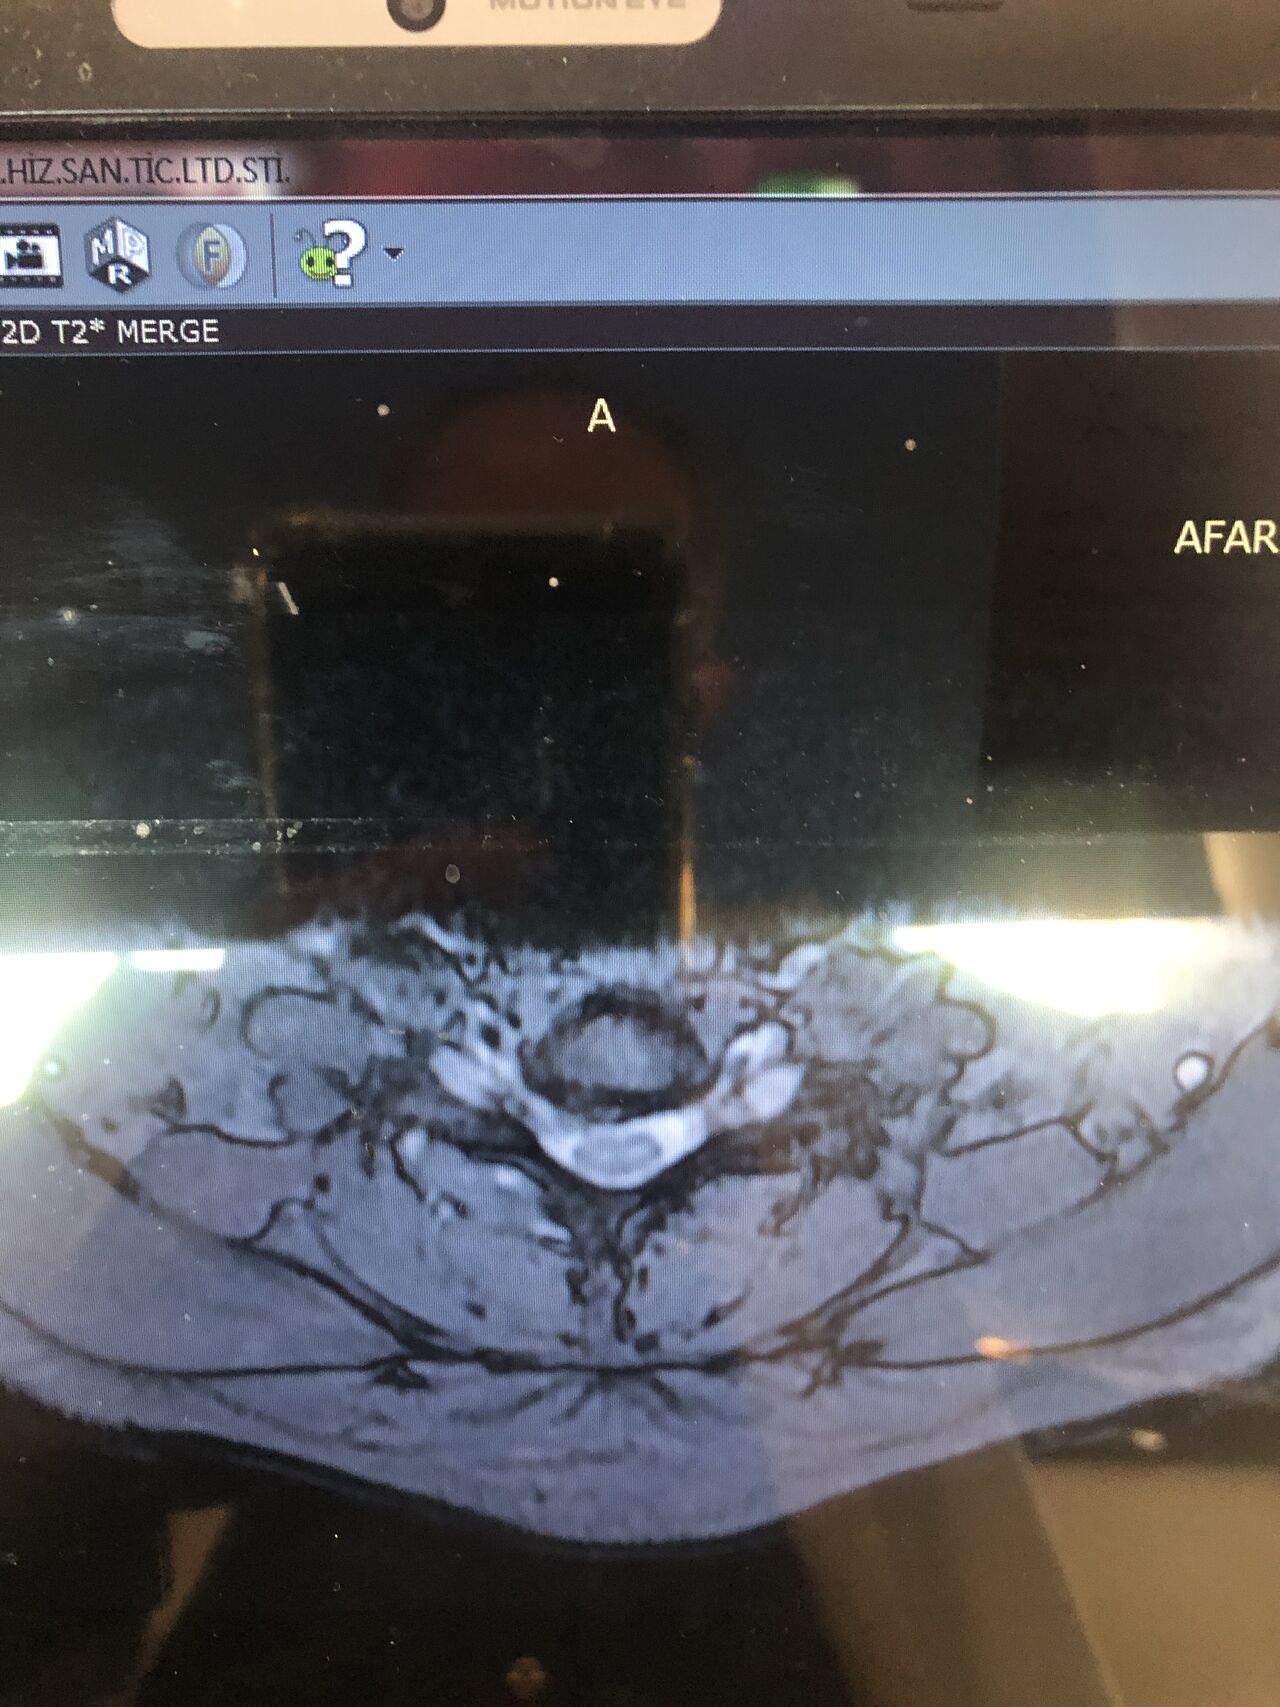

Case 9

42 years old female presented to my clinic yesterday on May15/2025 with chronic Low back for 2 yrs. She is from afghanestan and arrived to tehran 3 month ago. Visited pain specialist 3 months ago who just did PPD test and gave her Anti TB medication. In examination just had severe focal khyphosis from L3 to L5 without any tenderness. Her mri was done 2 months ago. Report is in Farsi and mentions of paraspinal puss/ fluid collection esp in psoas muscles, with extension of fluid collection to R pelvic region. Had 2 site of severe canal stenosis due to previous fractures of L3,4,5 and movement of fractured bones to the canal with complete distractions of those levels discs with fusion of L3 to L5

I ordered C T scan of lumbar and pelvic MRI / chest x r and reffered her to neurosurgon and infectious disease specialist to get full assessment and possible hospitalized for biopsy and surgery